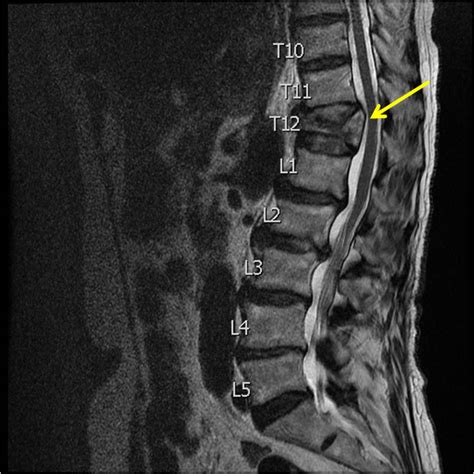

Imaging Tests

Imaging tests are crucial for confirming the diagnosis and determining the severity of the fracture.

- MRI Scans: MRIs are useful for evaluating soft tissues, such as ligaments and spinal cord. They can help detect nerve compression or other complications.